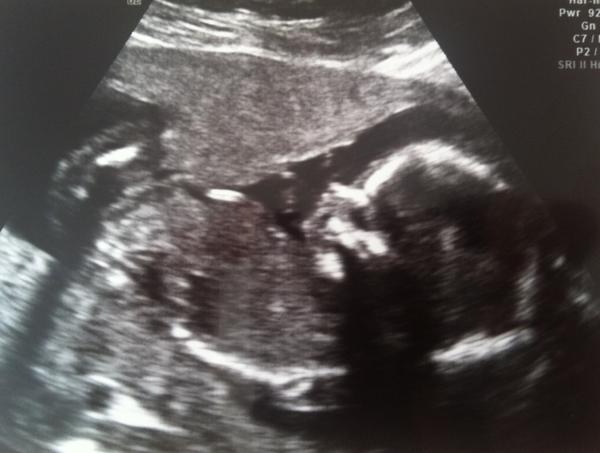

Had our 20wk scan yesterday. Everything is fine with our Alien, everything seems to be where it should be. We're keeping the gender a surprise.

Quick 10 minute scan this morning; just long enough to tell us... It's a boy! Thrilled - it's made it so much more real!